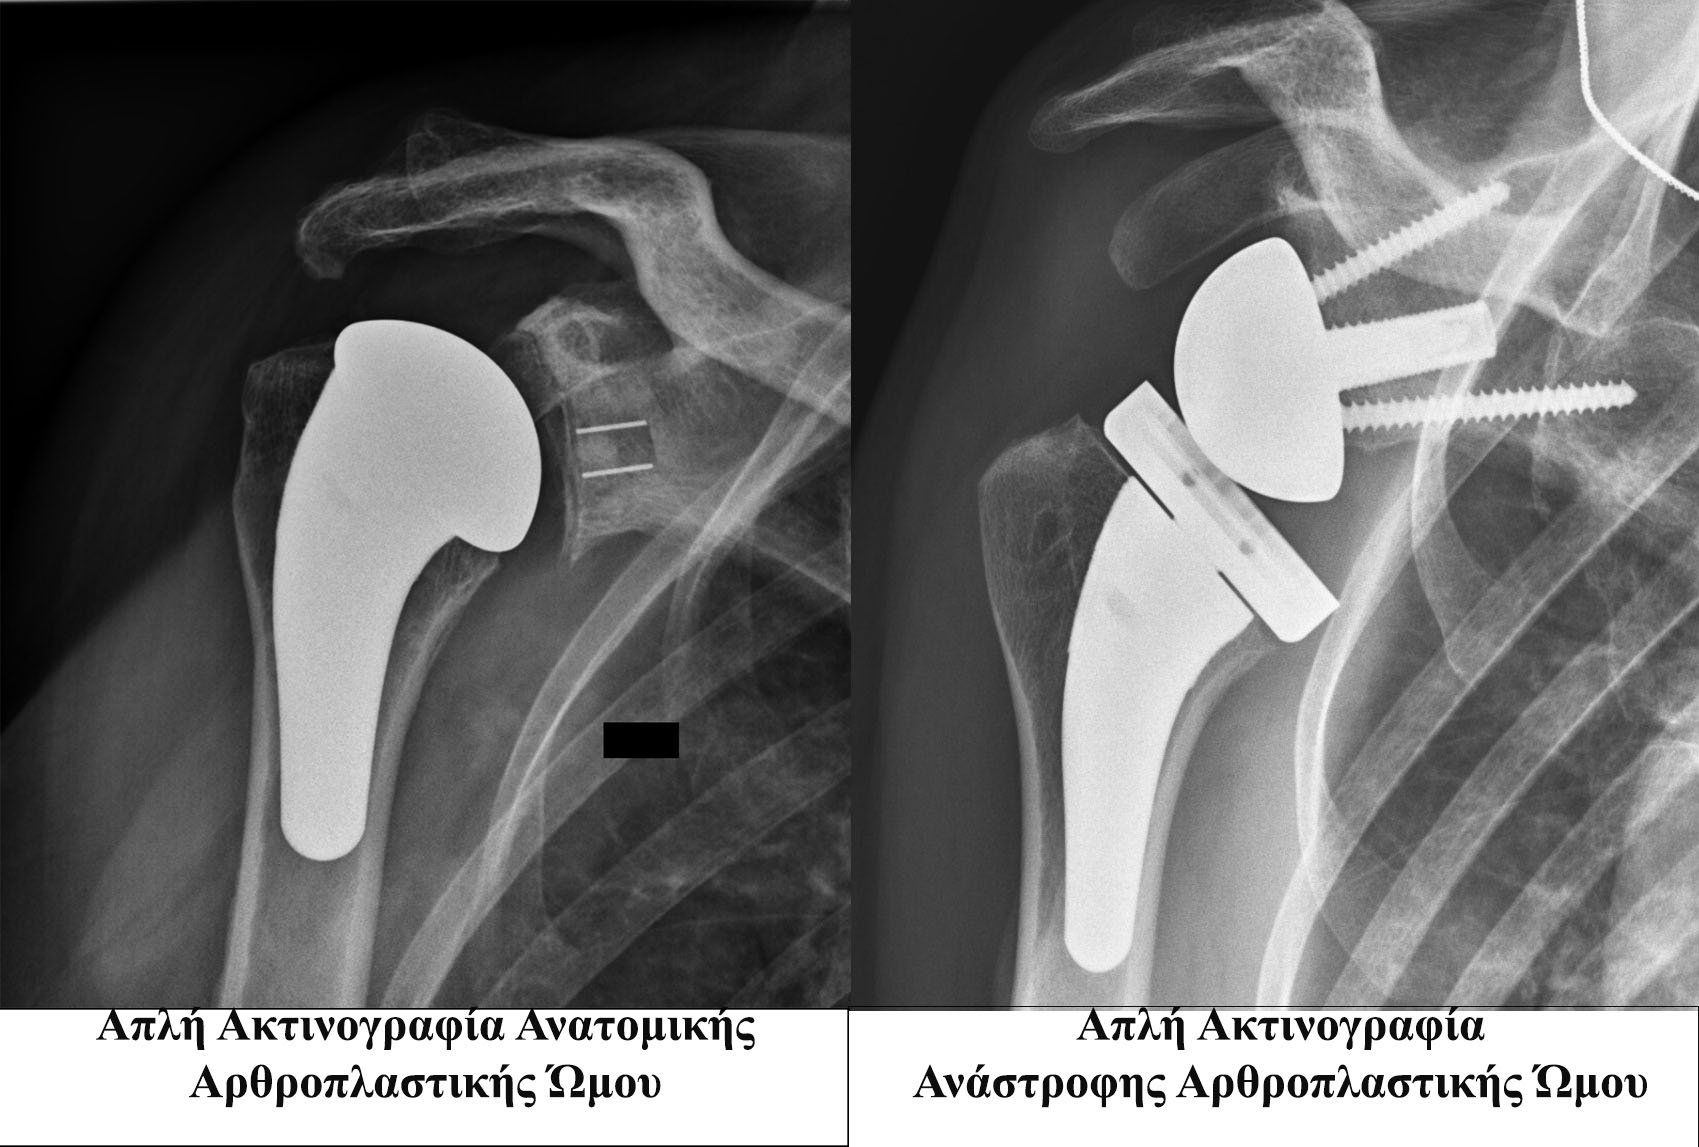

Η διάγνωση της αρθρίτιδας του ώμου στηρίζεται κυρίως στα εξής: